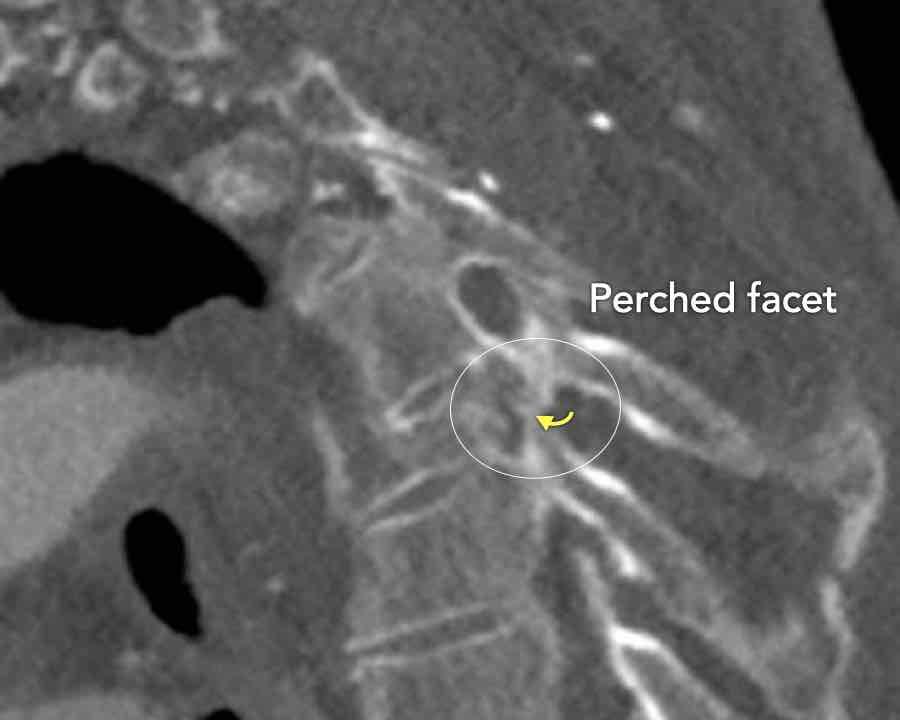

Scroll through the images

Findings:

- Perched facet joints (yellow curved arrows), so think of C injury.

- Posterior displacement of the vertebral bodies in the midline.

- Secondary A4 injury of the vertebral body.

Conclusion

Type C + A4 injury